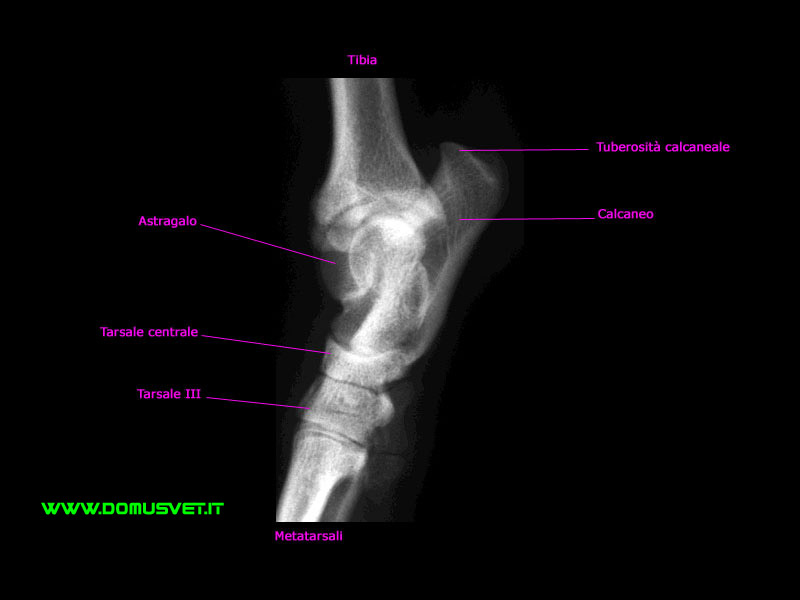

Atlante Radiografico del cane: Tarso LL

Tarso LL